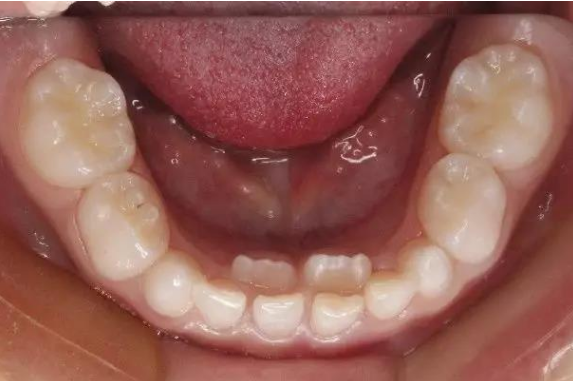

孩子嘴里冒出“双排牙”,既影响笑容颜值,又导致牙齿排列不齐、清洁困难,甚至会影响孩子的颌骨发育!家长应及时干预并科学应对,这份“双排牙”应对指南请收好!

“双排牙”医学上称为乳牙滞留,指恒牙已萌出但乳牙未按时脱落,导致新、旧牙齿重叠排列。主要原因有3点:

(一)牙齿重叠:门牙、侧门牙等部位,新牙从乳牙内侧或外侧萌出,形成“两层牙齿”。